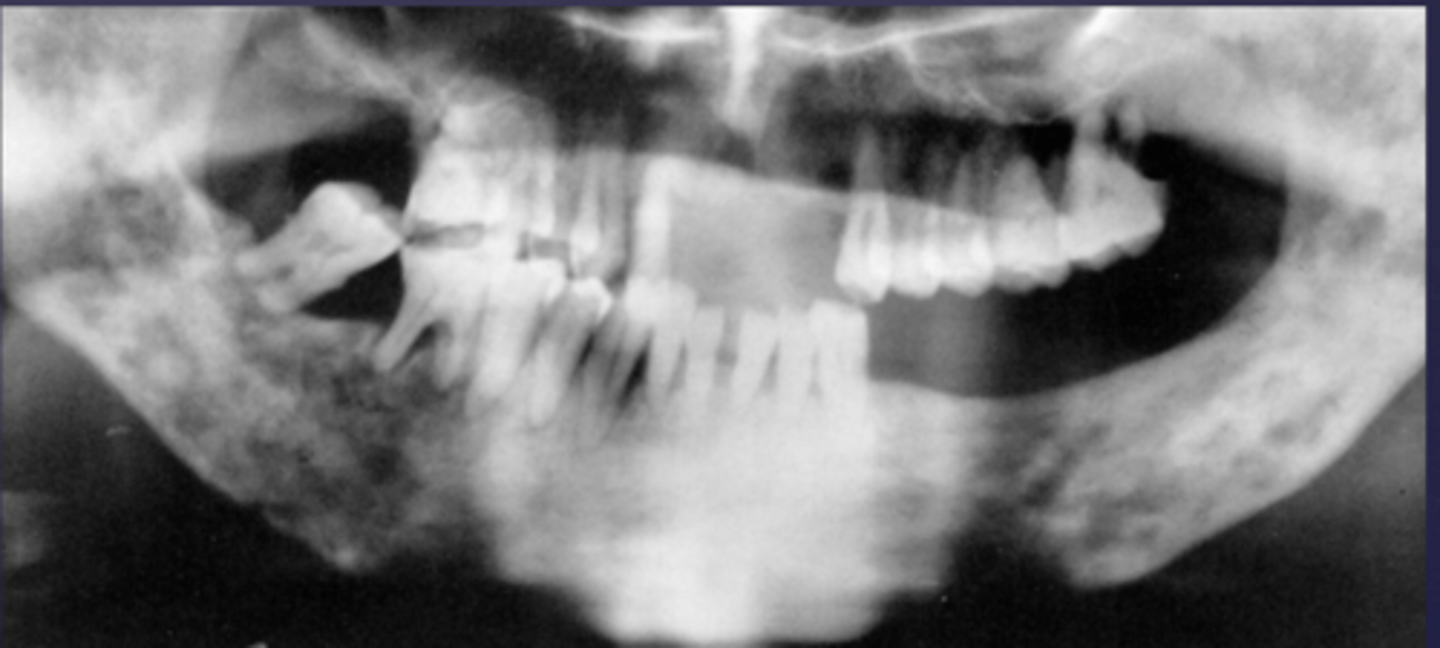

How would you describe the lesion?

- Well-defined corticated multilocular radiolucency in the right ramus

- Mandibular body causing root resorption

- Expansion and thinning of anterior wall of ramus, coronoid process, inferior border of mandible

- Displacement of the inferior alveolar canal

What category would this lesion be part of?

Benign

What would be a differential diagnosis for this lesion?

- Ameloblastoma

- OKC